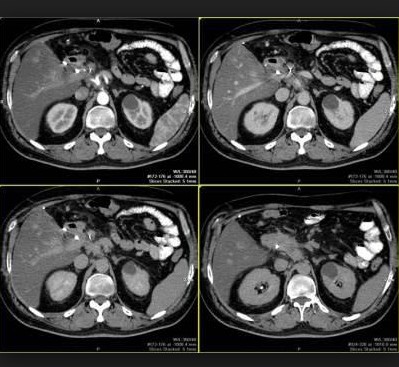

Одним из наиболее информативных видов скрининга органов брюшной полости и забрюшинного пространства является мультиспиральная компьютерная томография. Она позволяет изучать анатомическое состояние поджелудочной железы, печени, селезенки, желчного пузыря и протоков, а также органов забрюшинного пространства – почек, надпочечников, сосудов, мочевыводящей системы и лимфоидной ткани. В область обследования также попадают нижние доли легких и сердце, сосуды большого круга кровообращения и некоторые позвонки грудного и поясничного отделов позвоночника.

На практике чаще всего КТ направлена на выявление объемных процессов внутренних органов, в частности, полипов, кист, опухолей, конкрементов, абсцессов. КТ имеет большое значение для дифференцирования очаговых поражений поджелудочной железы и печени, в данном случае исследование часто проводится с контрастированием. Многофазное исследование в артериальную и портально-венозную фазы контрастного усиления позволяет характеризовать очаговые изменения и оценивать возможности консервативного и оперативного лечения.

Перед обследованием пациент должен снять с себя металлические предметы, т.к. они вызывают на снимках различные артефакты. КТ брюшной полости выполняется в положении пациента лежа на спине на столе томографа. Подвижный стол аппарата вместе с пациентом поступательно передвигается в кольцо, которое во время скрининга находится на уровне живота пациента. Сначала проводится нативное исследование, если его данных недостаточно для  определения заболевания и с целью уточнения выявленных нарушений процедура далее выполняется с многофазным контрастным болюсным усилением, при котором через локтевую вену пациента в кровь вводится контрастный препарат.

Такой режим сканирования позволяет охватить больше параметров, выявить кровоизлияния, новообразования, воспалительные и другие процессы. Отметим, что порядка 80% обследований брюшной полости проводится с контрастным усилением.